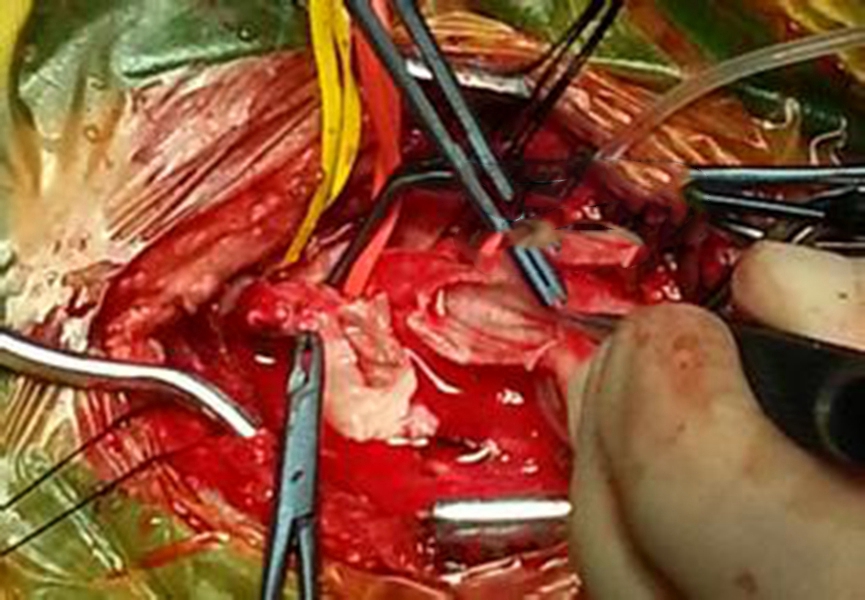

幼兒煙霧病腦手術

幼兒頸部手術煙霧病

幼兒頭部手術煙霧病

A:煙霧病目前有兩種手術方式,分別是血管搭橋手術和血管貼敷手術。血管搭橋手術是將顳淺動脈進行剝離,然後與大腦中動脈進行吻合搭橋。而血管貼敷手術是將顳淺動脈剝離後貼敷到腦的表面上。通過這兩種手術方式,主要的起到的作用是建立新的側枝循環,從而供應腦……